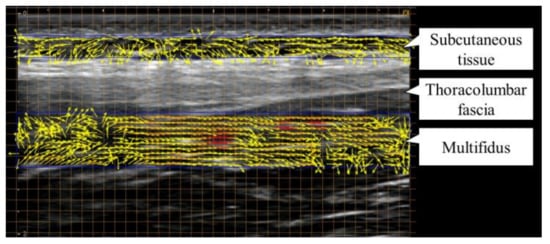

2.5. Measurement Method of Lumbar Myofascial Gliding